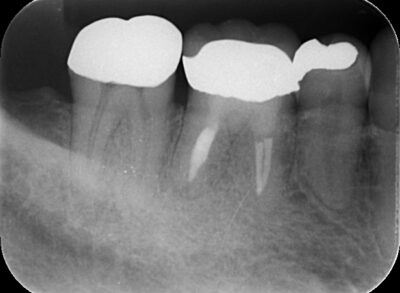

虫歯の最終形態、難治性根尖性歯周炎から歯を救う「歯根端切除術」や、グラグラの重度歯周病を改善する「歯周組織再生治療」など、世界基準の先進医療を日々実践しています。